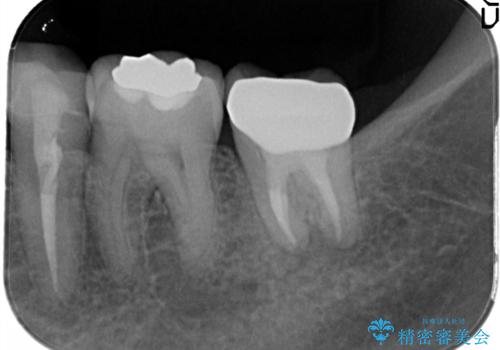

- 奥歯が痛いことを主訴に来院されました。

レントゲンにて根尖病変を認め、根管治療を行ったのちセラミッククラウンにて修復しました。根管治療は川島先生に依頼。

- 13万円(根管治療は別途)費用は治療当時の料金となります